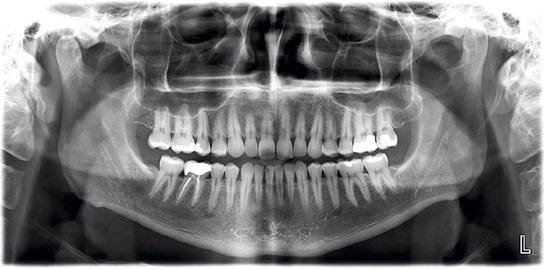

Rx Panorámica

Es un estudio esencial para la evaluación inicial, planificación de tratamientos odontológicos y seguimiento clínico.

Nuestras radiografías panorámicas 2D permiten una visualización completa de ambas arcadas dentales, estructuras óseas y articulaciones, con una excelente calidad diagnóstica y baja dosis de radiación